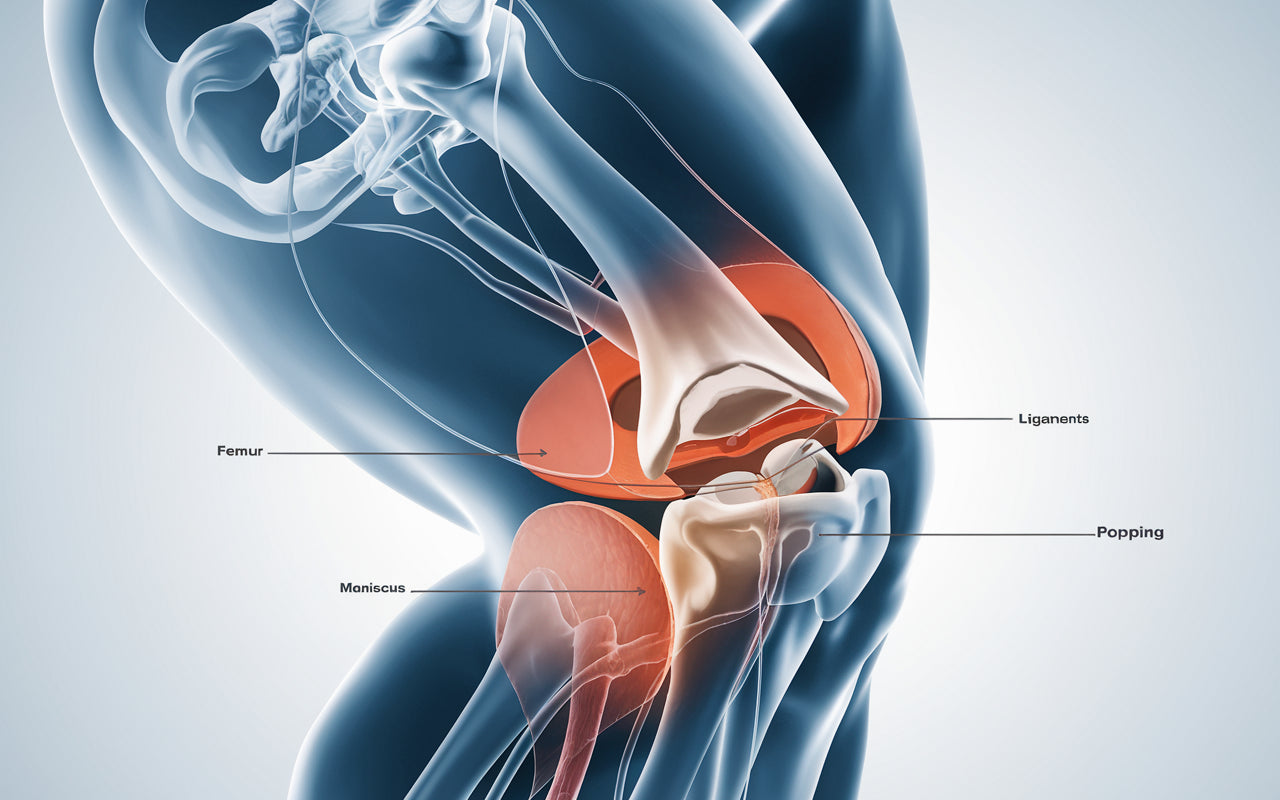

Knäleden är en av kroppens mest komplexa leder och utsätts dagligen för stor belastning. Knäproblem kan drabba personer i alla åldrar och uppstår av många olika orsaker.